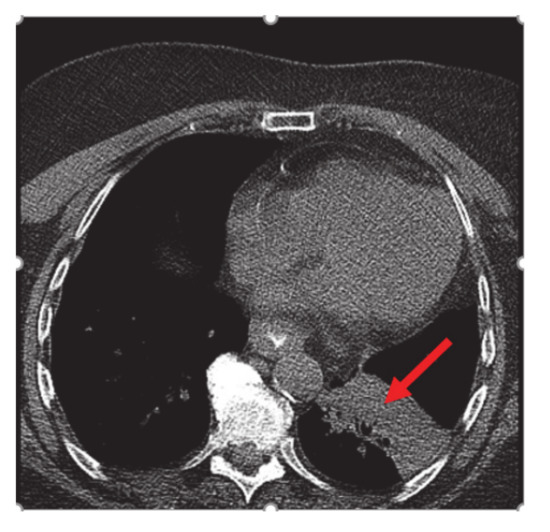

Bronchoscopy revealed endobronchial lesion involving the takeoff of the left lower lobe. PET scan showed left lower lobe hypermetabolic mass causing bronchial obstruction, distal collapse, and consolidation of basilar segments as well as subcarinal lymphadenopathy, osteolytic destruction of left acetabulum pubis, superior pubic ramus, and L3 vertebral body (Figure 2).

Figure 2.

Nuclear Medicine Positron Emission Tomography/Computer Tomography (NM PET/CT): left lower lobe hypermetabolic neoplasm (red arrow) causing bronchial obstruction and distal collapse. Metastatic mediastinal adenopathy. Not shown, L3 vertebral body, left acetabulum pubis, and superior pubic ramus metastasis.